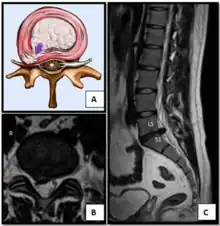

Lumbar disc lesions, classification -

Normal situation and spinal disc herniation in cervical vertebrae -

Illustration depicting herniated disc and spinal nerve compression -

Nucleus herniating through tear in annulus (with MRI)[8] -

Illustration showing disc degeneration, prolapse, extrusion and sequestration.

- Magnetic resonance imaging is the gold standard study for confirming a suspected LDH. With a diagnostic accuracy of 97%, it is the most sensitive study to visualize a herniated disc due to its significant ability in soft tissue visualization. MRI also has higher inter-observer reliability than other imaging modalities. It suggests disc herniation when it shows an increased T2-weighted signal at the posterior 10% of the disc. Degenerative disc diseases have shown a correlation with Modic type 1 changes. When evaluating for postoperative lumbar radiculopathies, the recommendation is that the MRI is performed with contrast unless otherwise contraindicated. MRI is more effective than CT in distinguishing inflammatory, malignant, or inflammatory etiologies of LDH. It is indicated relatively early in the course of evaluation (<8 weeks) when the patient presents with relative indications like significant pain, neurological motor deficits, and cauda equina syndrome. Diffusion tensor imaging is a type of MRI sequence used for detecting microstructural changes in the nerve root. It may be beneficial in understanding the changes that occur after herniated lumbar disc compresses a nerve root, and might help in differentiating the patients that need surgical intervention. In patients with a high suspicion of radiculopathy due to lumbar disc herniation, yet the MRI is equivocal or negative, nerve conduction studies are indicated.[43] T2-weighted images allow for clear visualization of protruded disc material in the spinal canal.